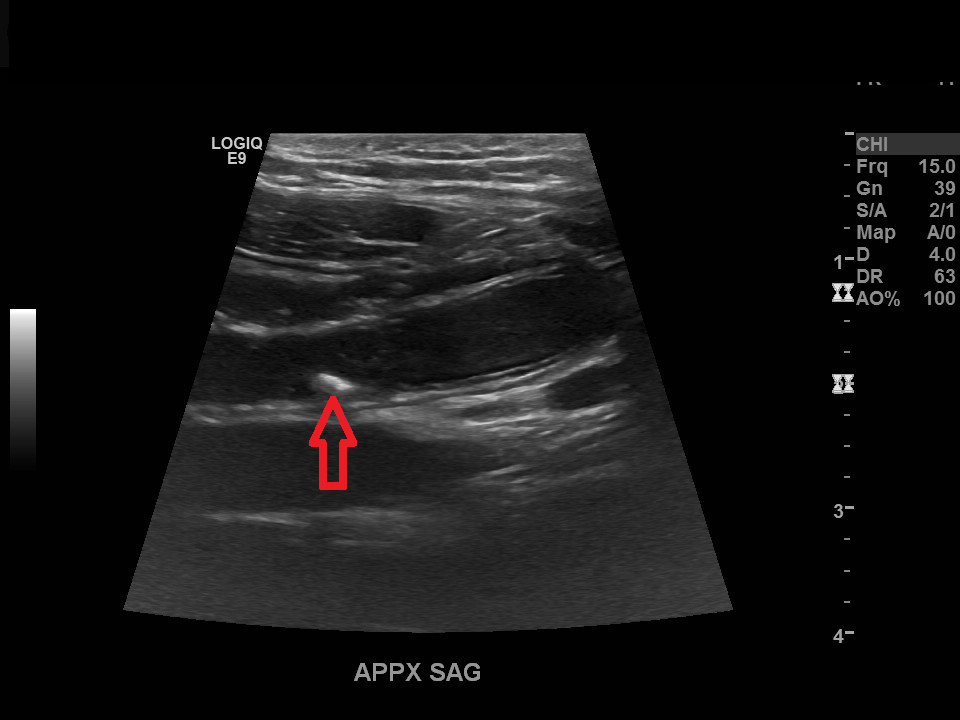

Appendicitis 4

1 cm appendicitis with hyperemia and appendicolith